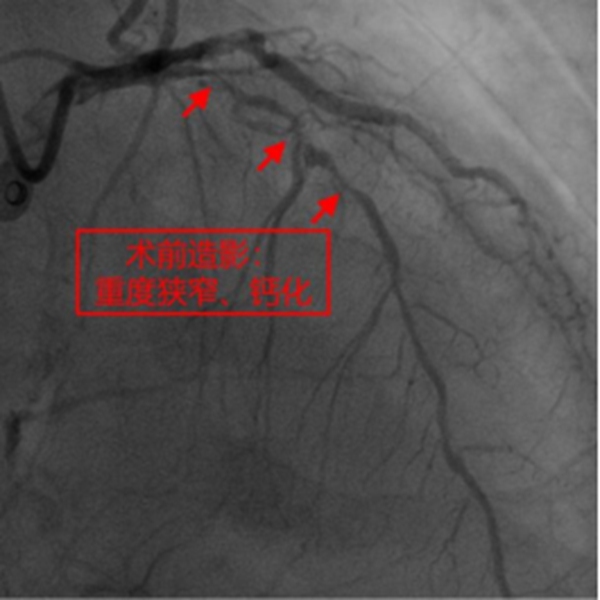

冉擘力主任介紹,患者為78歲男性,近年來常反復胸悶、氣短不適,合并心力衰竭、2型糖尿病、腎功能不全、貧血,多次因心力衰竭、肺部感染住院,不能正常生活。1月前患者曾行冠脈造影提示三支血管病變并對回旋支植入支架,但其中前降支嚴重鈣化伴重度狹窄,手術難度極大。冉擘力主任看到患者的造影結果后認為患者高齡、合并癥多、冠脈病變復雜,行外科冠脈搭橋風險較高,建議微創介入完成手術,術前組織了全院多學科會診評估病情、討論圍術期治療方案。經冠脈介入團隊崔坤副主任醫師、蒲云飛副主任醫師、王方超主治醫師多次討論,考慮冠脈彌漫性重度狹窄伴環形鈣化,決定采用Rota-Shock(旋磨+Shockwave)策略,處理冠脈彌漫且嚴重鈣化病變。

在征得患者及家屬同意,做好充分術前準備的情況下,冠脈介入團隊在冉擘力主任帶領下,按計劃給患者實施了血管內超聲(IVUS)指導下經皮冠脈旋磨+Shockwave沖擊波球囊碎裂鈣化斑塊及支架植入術,術中團隊克服了一系列困難,最終安全順利地完成了全部介入手術過程,完全碎裂了環狀鈣化斑塊,效果非常滿意,歷時約1個多小時,手術成功,病人安返病房。術后患者胸悶、氣短明顯緩解,對治療效果十分滿意。